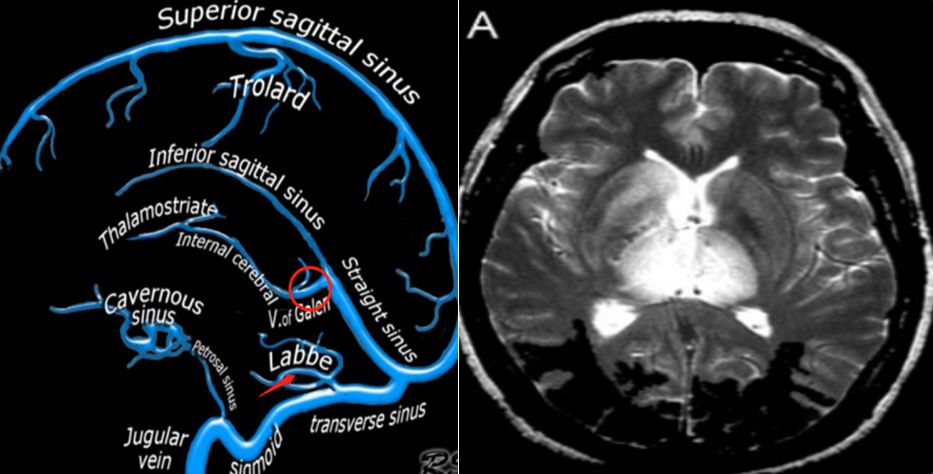

(左图来源于北美放射学教学网站文献7,红圈标识处提示galen静脉,红

3 galen静脉动脉瘤样畸形磁共振成像 a.